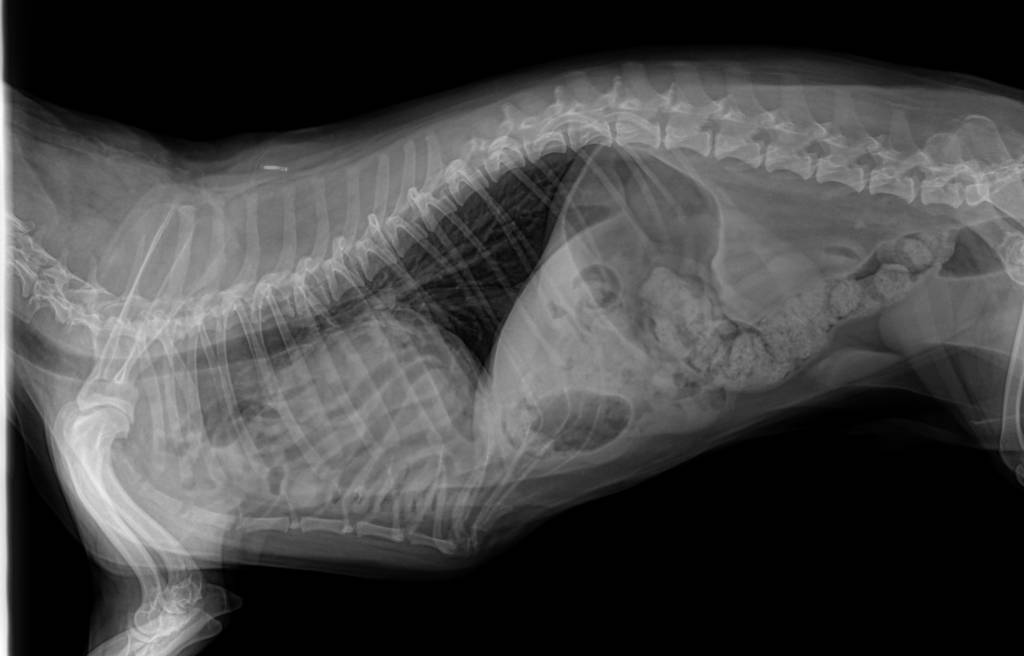

Why is this Pekingese vomiting?

1. Intestinal loops are superimposed to the cardiac silhouette. Meanwhile, there are few intestinal loops in the abdomen.

2. Peritoneo-pericardial diaphragmatic hernia (PPDH).

3. During laparotomy, intestinal loops and other viscera are gently pulled into the abdomen, and the hernia is sutured.

4. This is a tricky but vital question. Many PPDHs are incidental findings. After all, this patient has been living with a hernia for 10 years. The challenge is to be convinced that the hernia is truly the cause of the vomiting before surgery is considered.